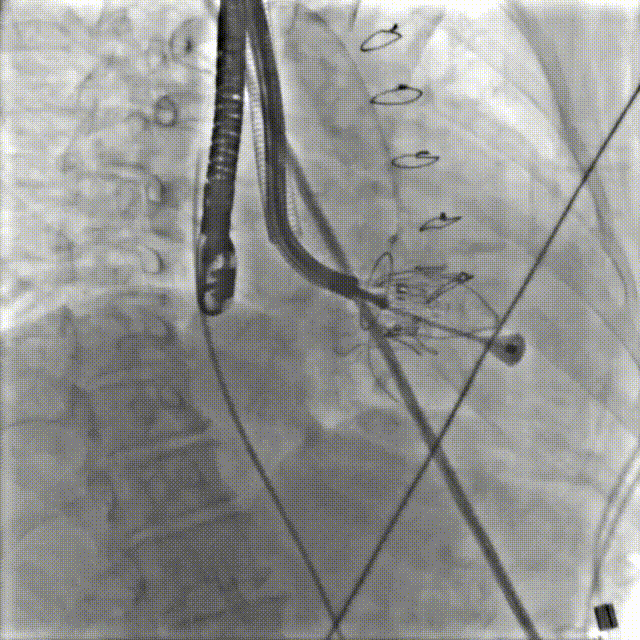

手术在患者全麻状态下进行,采用经右侧颈静脉作为入路,将装载有人工瓣膜的输送器缓慢推送至右心房;并在经食道超声和DSA的引导下小心调整输送器角度,将输送器送入右心室;逐步释放瓣膜锚定装置和盘片,调整瓣膜位置后,锚定瓣膜完成植入。术后右房压明显下降,从术前的25/10(16) mmHg降至术后即刻的12/7(10) mmHg,术后超声提示人工三尖瓣同轴性良好,固定牢固,无反流及瓣周漏手术室即刻拔除气管插管。